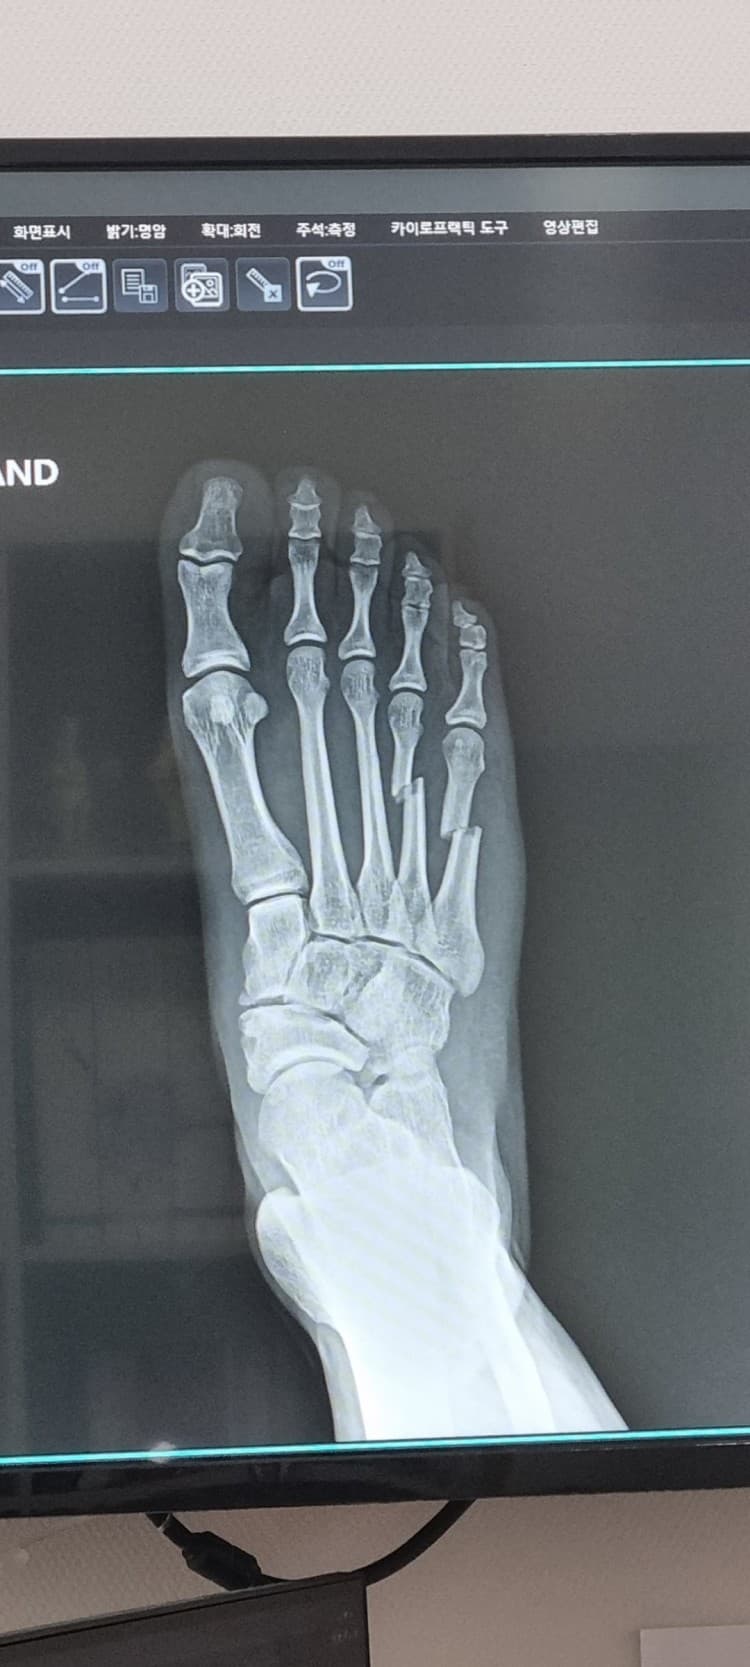

안녕하세요 MMA 스파링도중 발등뼈가 부러졌습니다.

또 아래 사진정도면 신체검사시 감점때문에 그런데 비수술로는 회복이 어려울까요?

개개인마다 회복력이나 회복 과정에서 발생하는 여러가지 요인에 의해서 회복에 걸릴 시간이 천차만별로 다르기 때문에 현재로서는 정확하게 알기 어렵습니다. 다만, 일반적으로 수술 후 회복에 있어서는 최소 2-3개월이 소요되는 만큼 12월까지 68일만에 뛸 정도로 회복이 가능하지 못할 가능성이 더 높습니다. 비수술적으로 회복을 하더라도 시간은 오래 걸리는데, 현재 상태에서 뼈가 많이 어긋나 있는데 수술을 하지 않을 경우 회복 기간이 중요할 것이 아니라 걷는 것과 뛰는 기능 자체에 문제가 생길 우려가 있습니다.